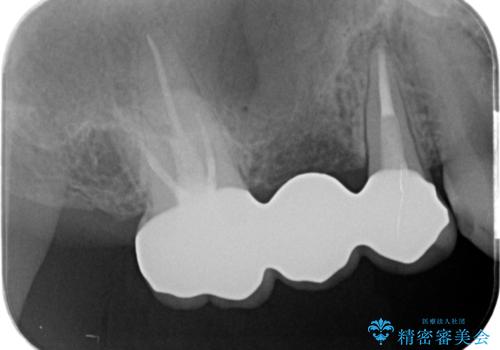

- 39.6万円(ジルコニアクラウン×3・仮歯×3)費用は治療当時の料金となります

ジルコニアブリッジは、インプラントと違い手術の必要がなく審美的に咬合機能の回復ができる補綴手段です。